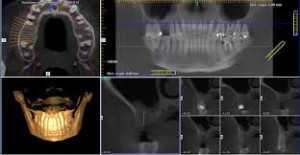

Vantaggi della radiografia 3D

La radiografia 3D offre al dentista informazioni dettagliatissime per una diagnostica più esatta e una maggiore precisione di trattamento. La radiografia 3D offre una visione completa sull’anatomia maxillo-facciale, quasi da ogni angolo e in quasi ogni prospettiva. Informazioni che non vi sarebbero mai disponibili con le sole immagini in 2D.